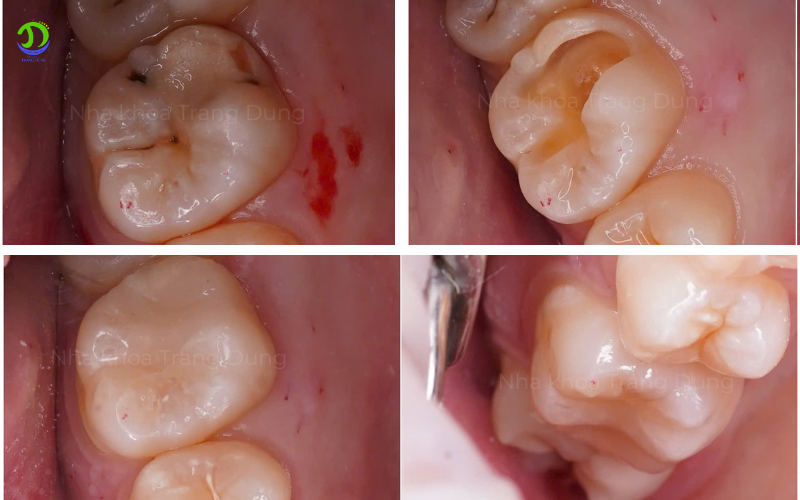

Các phương pháp điều trị răng sâu phổ biến hiện nay

Trám răng thẩm mỹ (Áp dụng cho sâu răng nhẹ)

Đây là giải pháp vàng cho giai đoạn đầu. Bác sĩ sẽ làm sạch hoàn toàn vùng mô bị viêm nhiễm, sau đó sử dụng vật liệu Composite cao cấp để lấp đầy lỗ hổng. Quá trình này diễn ra cực kỳ nhanh chóng (chỉ từ 15-30 phút), khôi phục lại 100% hình dáng và màu sắc tự nhiên của răng. Tại Nha khoa Trang Dung, chúng tôi cam kết quy trình trám răng hoàn toàn không đau, không ê buốt nhờ kỹ thuật gây tê bề mặt tiên tiến.